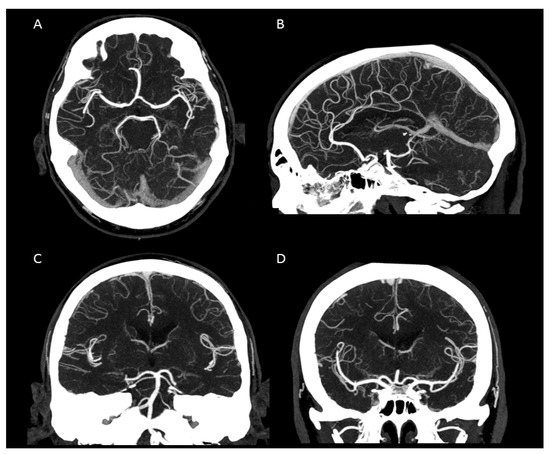

Figure 3.

Maximum intensity projection of an intracranial UHR-CTA. (A) axial plane. (B) sagittal plane. (C,D) coronal plane. Note the clear traceability/visualization of the circle of Willis and even the small peripheral vessel branches.

We were able to show that excellent image qualities were generated even though radiation exposure could be kept at explicitly moderate levels [10]. In addition, the occurrence of Hounsfield artefacts that frequently hinder the assessment of the vertebrobasilar system and the brainstem were also considerably low, enabling an advanced image interpretability. Both quantitative and qualitative evaluation of the UHR-CTAs confirmed our hypothesis of a highly remarkable improvement in image quality and spatial resolution. In particular, a high vascular contrast and a distinctly defined demarcation of the extracranial as well as the intracranial vessels could be demonstrated. It is noteworthy that even the smallest perforating arteries (e.g., LSA, as shown in Figure 3) vascularizing the deep brain structures become diagnostically accessible by UHR-CTA, which is generally not the case when using conventional CTA.